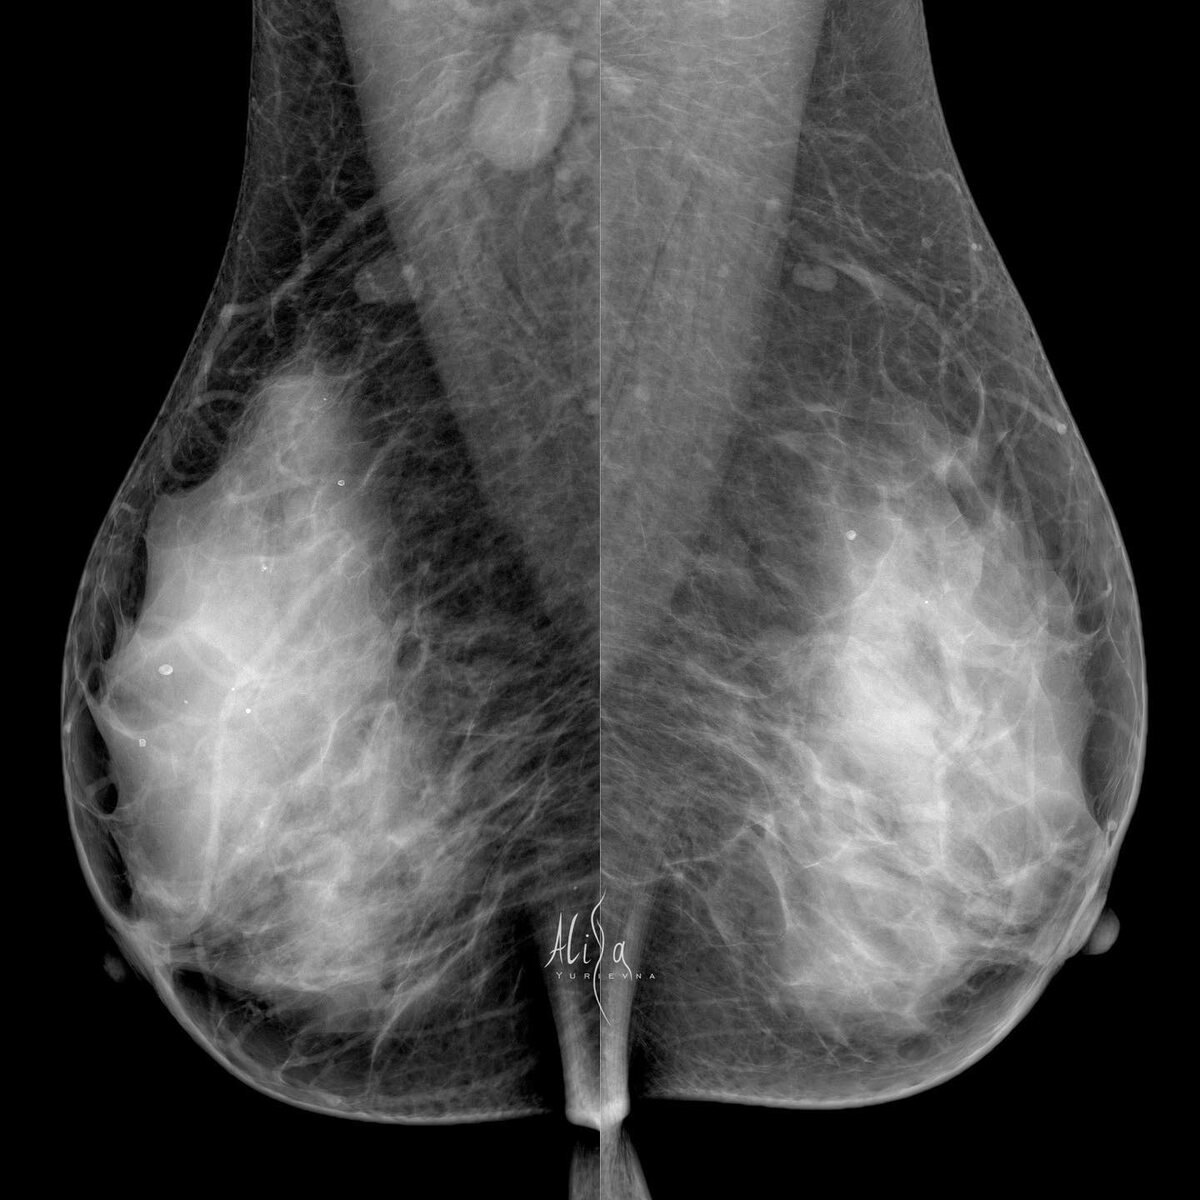

Кейс. Пациентка 38 лет

Плотный рентгенологический фон. Именно он порой не дает нам увидеть на маммограмме образования. Именно он повышает риск развития карциномы молочной железы. Именно при такой структуре железы обязательно назначается узи, которому плотный фон не помеха. Помощниками нам здесь, конечно, являются измененные лимфатические узлы справа. Видя их, ищем причину в молочной железе. И видим «выбухание» переднего контура паренхимы в косой проекции. Именно там и сидит виновник метастазов в аксиллярной зоне. Трипл, конечно же. Инвазивная карцинома G3, ИГХ: ER( 0 ) PR( 0 ) HER2neu ( 0 ) Кi67 30-40%

Помощниками нам здесь, конечно, являются измененные лимфатические узлы справа. Видя их, ищем причину в молочной железе. И видим «выбухание» переднего контура паренхимы в косой проекции. Именно там и сидит виновник метастазов в аксиллярной зоне.